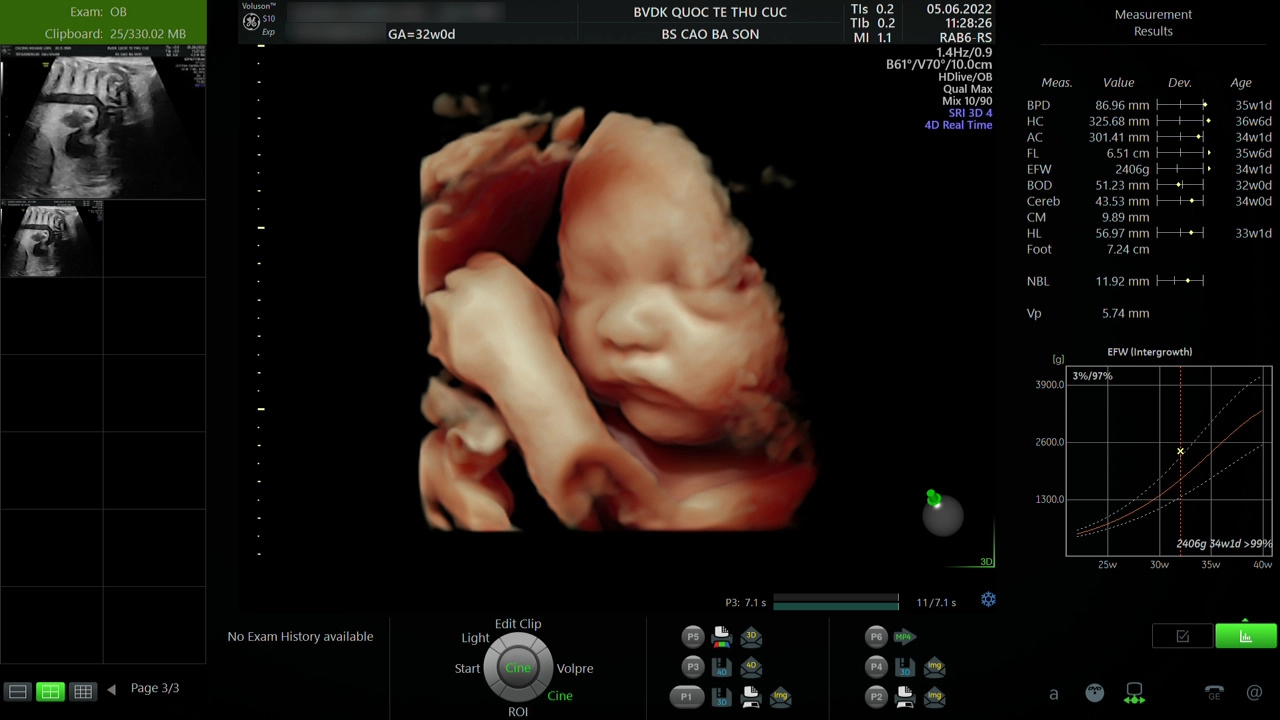

Hiện nay, có rất nhiều phương pháp siêu âm thai để mẹ bầu lựa chọn như siêu âm 2D, siêu âm 3D, siêu âm 4D, siêu âm 5D; trong đó siêu âm 5D là phương pháp siêu âm hiện đại, cho hình ảnh sắc nét, chân thực, đồng thời giúp phát hiện sớm dị tật thai nhi ngay từ những tuần đầu tiên.

Siêu âm thai 5D là phương pháp siêu âm hiện đại, cho hình ảnh thai nhi sắc nét, chân thực, đồng thời giúp phát hiện sớm dị tật thai nhi

Siêu âm thai tại Bệnh viện ĐKQT Thu Cúc mẹ sẽ được kiểm tra chi tiết tất tần tật các vấn đề thai kỳ, hạn chế bỏ sót các vấn đề của thai nhi bởi đội ngũ bác sĩ siêu âm giỏi. Bên cạnh đó, trang thiết bị siêu âm thai tại Thu Cúc TCI cũng là máy siêu âm 5D hiện đại cho kết quả siêu âm chính xác. Máy siêu âm 5D được trang bị ở tất cả các cơ sở tạo thuận tiện cho mẹ trong việc đi lại và thăm khám.